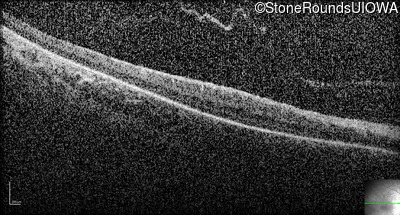

Optical Coherence Tomography - Right - No Light Perception

Exemplar / OCT Stack